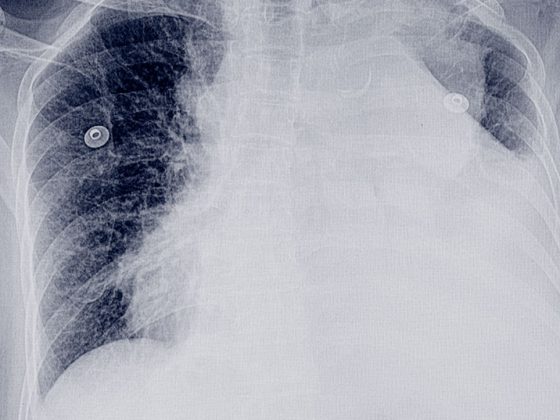

• Bildgebung bei der exazerbierten COPD

Infektexazerbierte COPD: Bildgebung zur Diagnostik und Risikobewertung